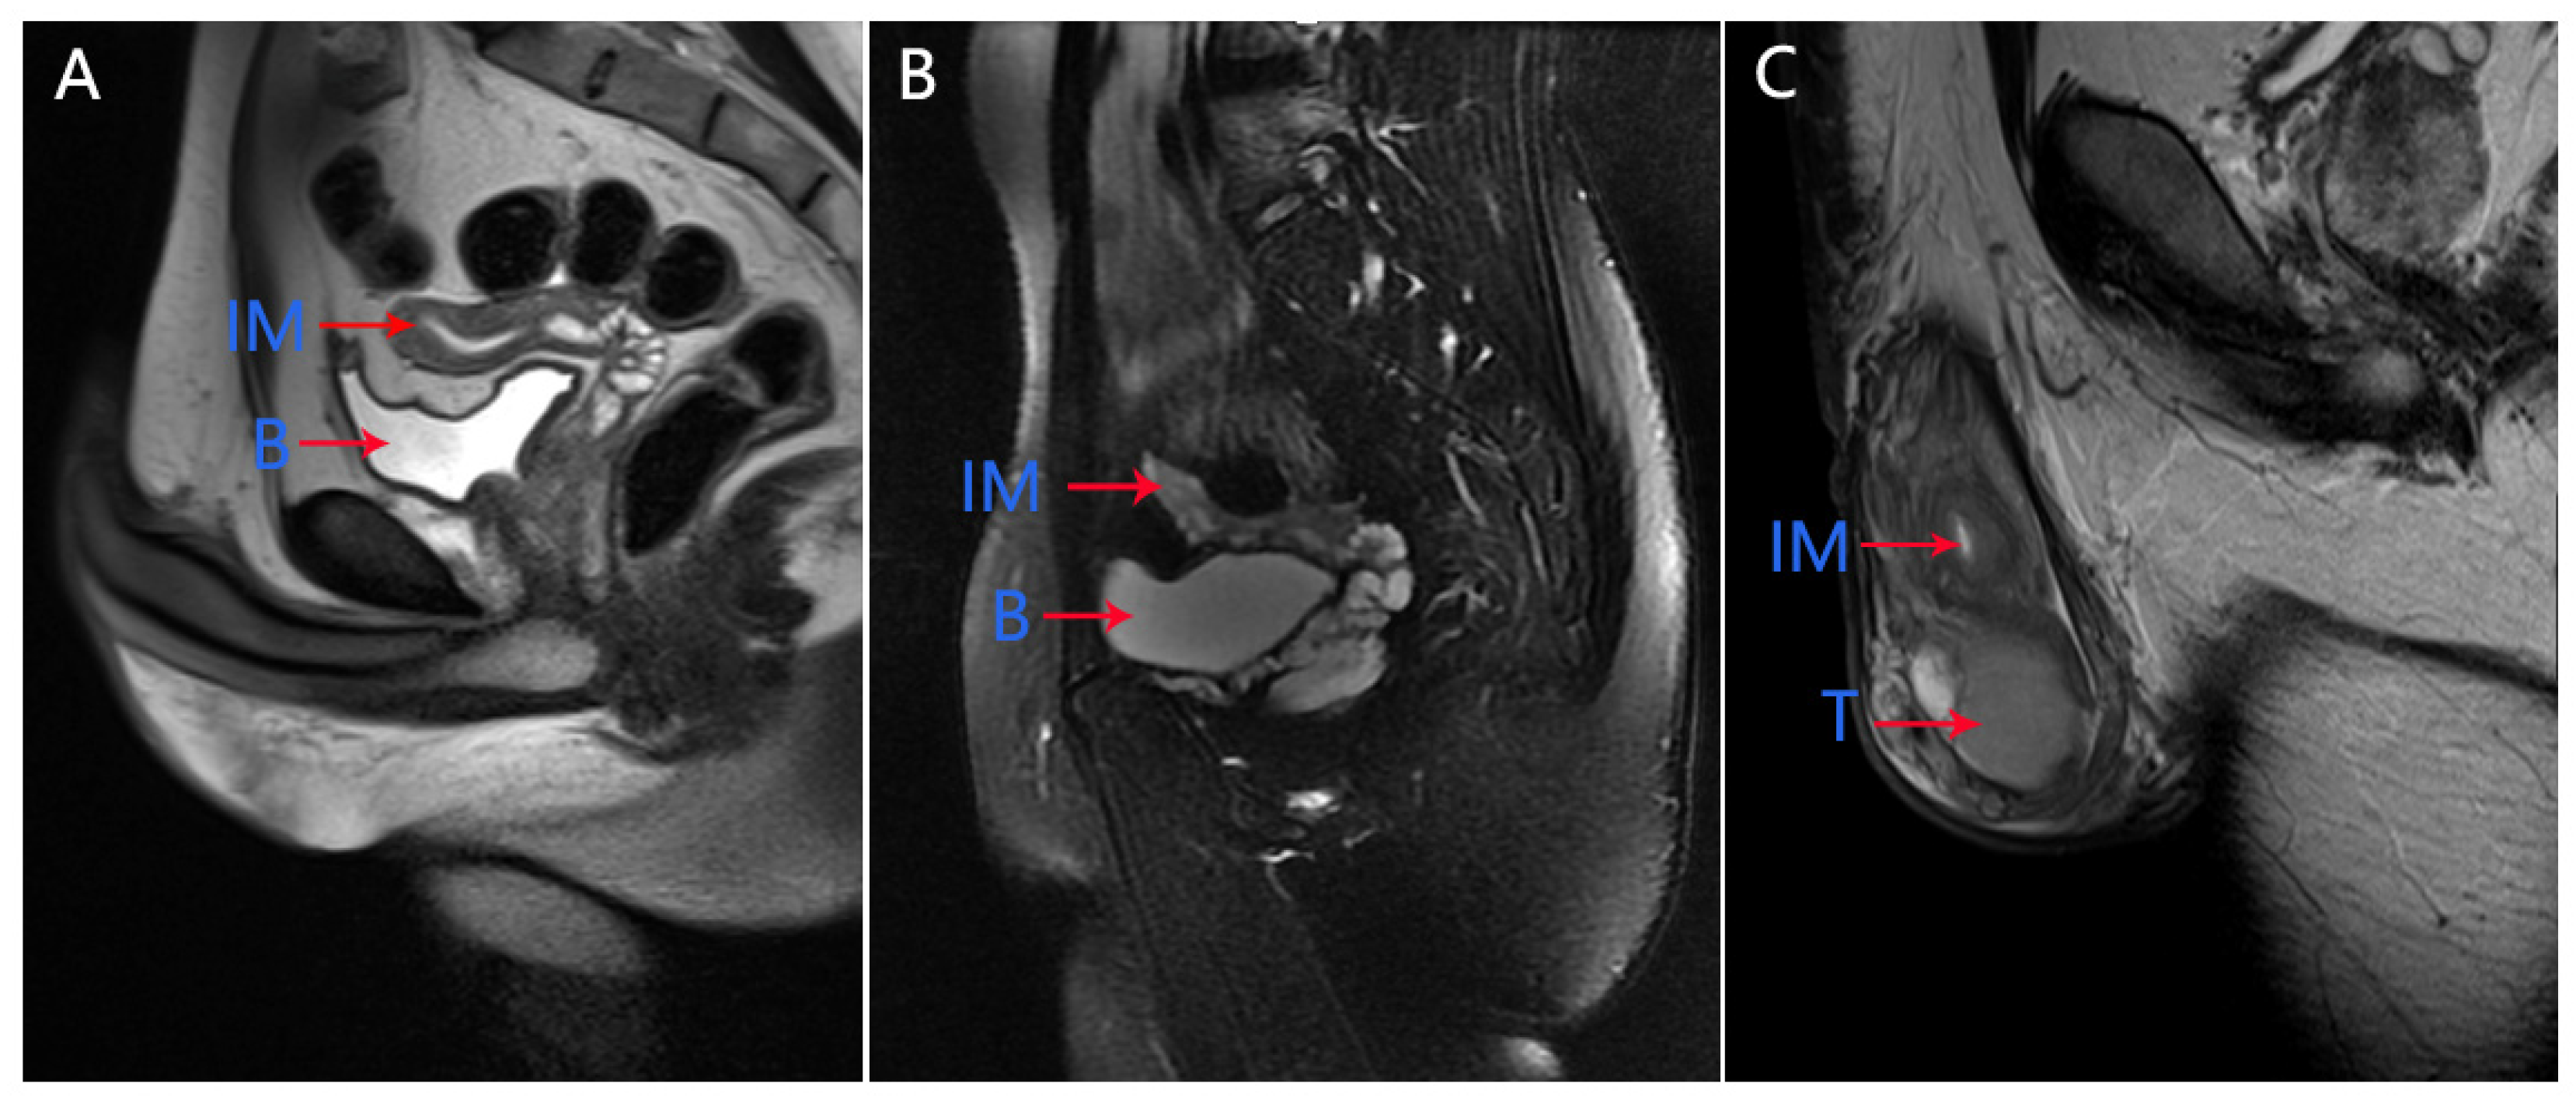

In our medical center, physical examination showed that the left testicle was palpable (10 mL) and the right testicle was impalpable. Penis and secondary sexual characteristics were well developed. The patient had the normal 46, XY karyotype. The serum AMH level was 0.06 ng/mL, which was significantly below the lower limit of the normal range (adult male: 2.04–19.22 ng/mL). Pelvic MRI showed the presence of uterus and upper two-thirds of the vagina at normal positions (Figure 1A). Micro-TESE was performed again, but no sperms were observed. Laparoscopic removal of Müllerian remnants was performed a week after the patient underwent micro-TESE. The patient was histologically confirmed to have PMDS (Figure 2A,B). Pathological examination of the patient revealed the presence of a normal uterus with uterine fibroids (Figure 2B).

Figure 1.

Pelvic magnetic resonance images of the three cases. Pelvic magnetic resonance images show Müllerian remnants in cases 1 (A), 2 (B), and 3 (C). IM, immature uterus; B, bladder; T, testis.

In our medical center, physical examination of the patient showed that both sides of the testicle were palpable (6 mL). Penis and secondary sexual characteristics were well developed. The patient had the normal 46, XY karyotype. Serum AMH level was 3.21 ng/mL. Pelvic MRI revealed an immature uterus at the normal position (Figure 1B). Micro-TESE was performed and sperms were observed; Müllerian remnants were removed laparoscopically. Seminal vesicles and uteri were observed through transurethral seminal vesiculoscopy combined with laparoscopy, and the uterus was found to be connected to the urethra, while one of the openings was found in the verumontanum. The patient was histologically confirmed to have PMDS (Figure 2C,D).

The patient had the normal 46, XY karyotype. Serum AMH level was 7.72 ng/mL. Pelvic MRI revealed the presence of an immature uterus at the normal position (Figure 1C).